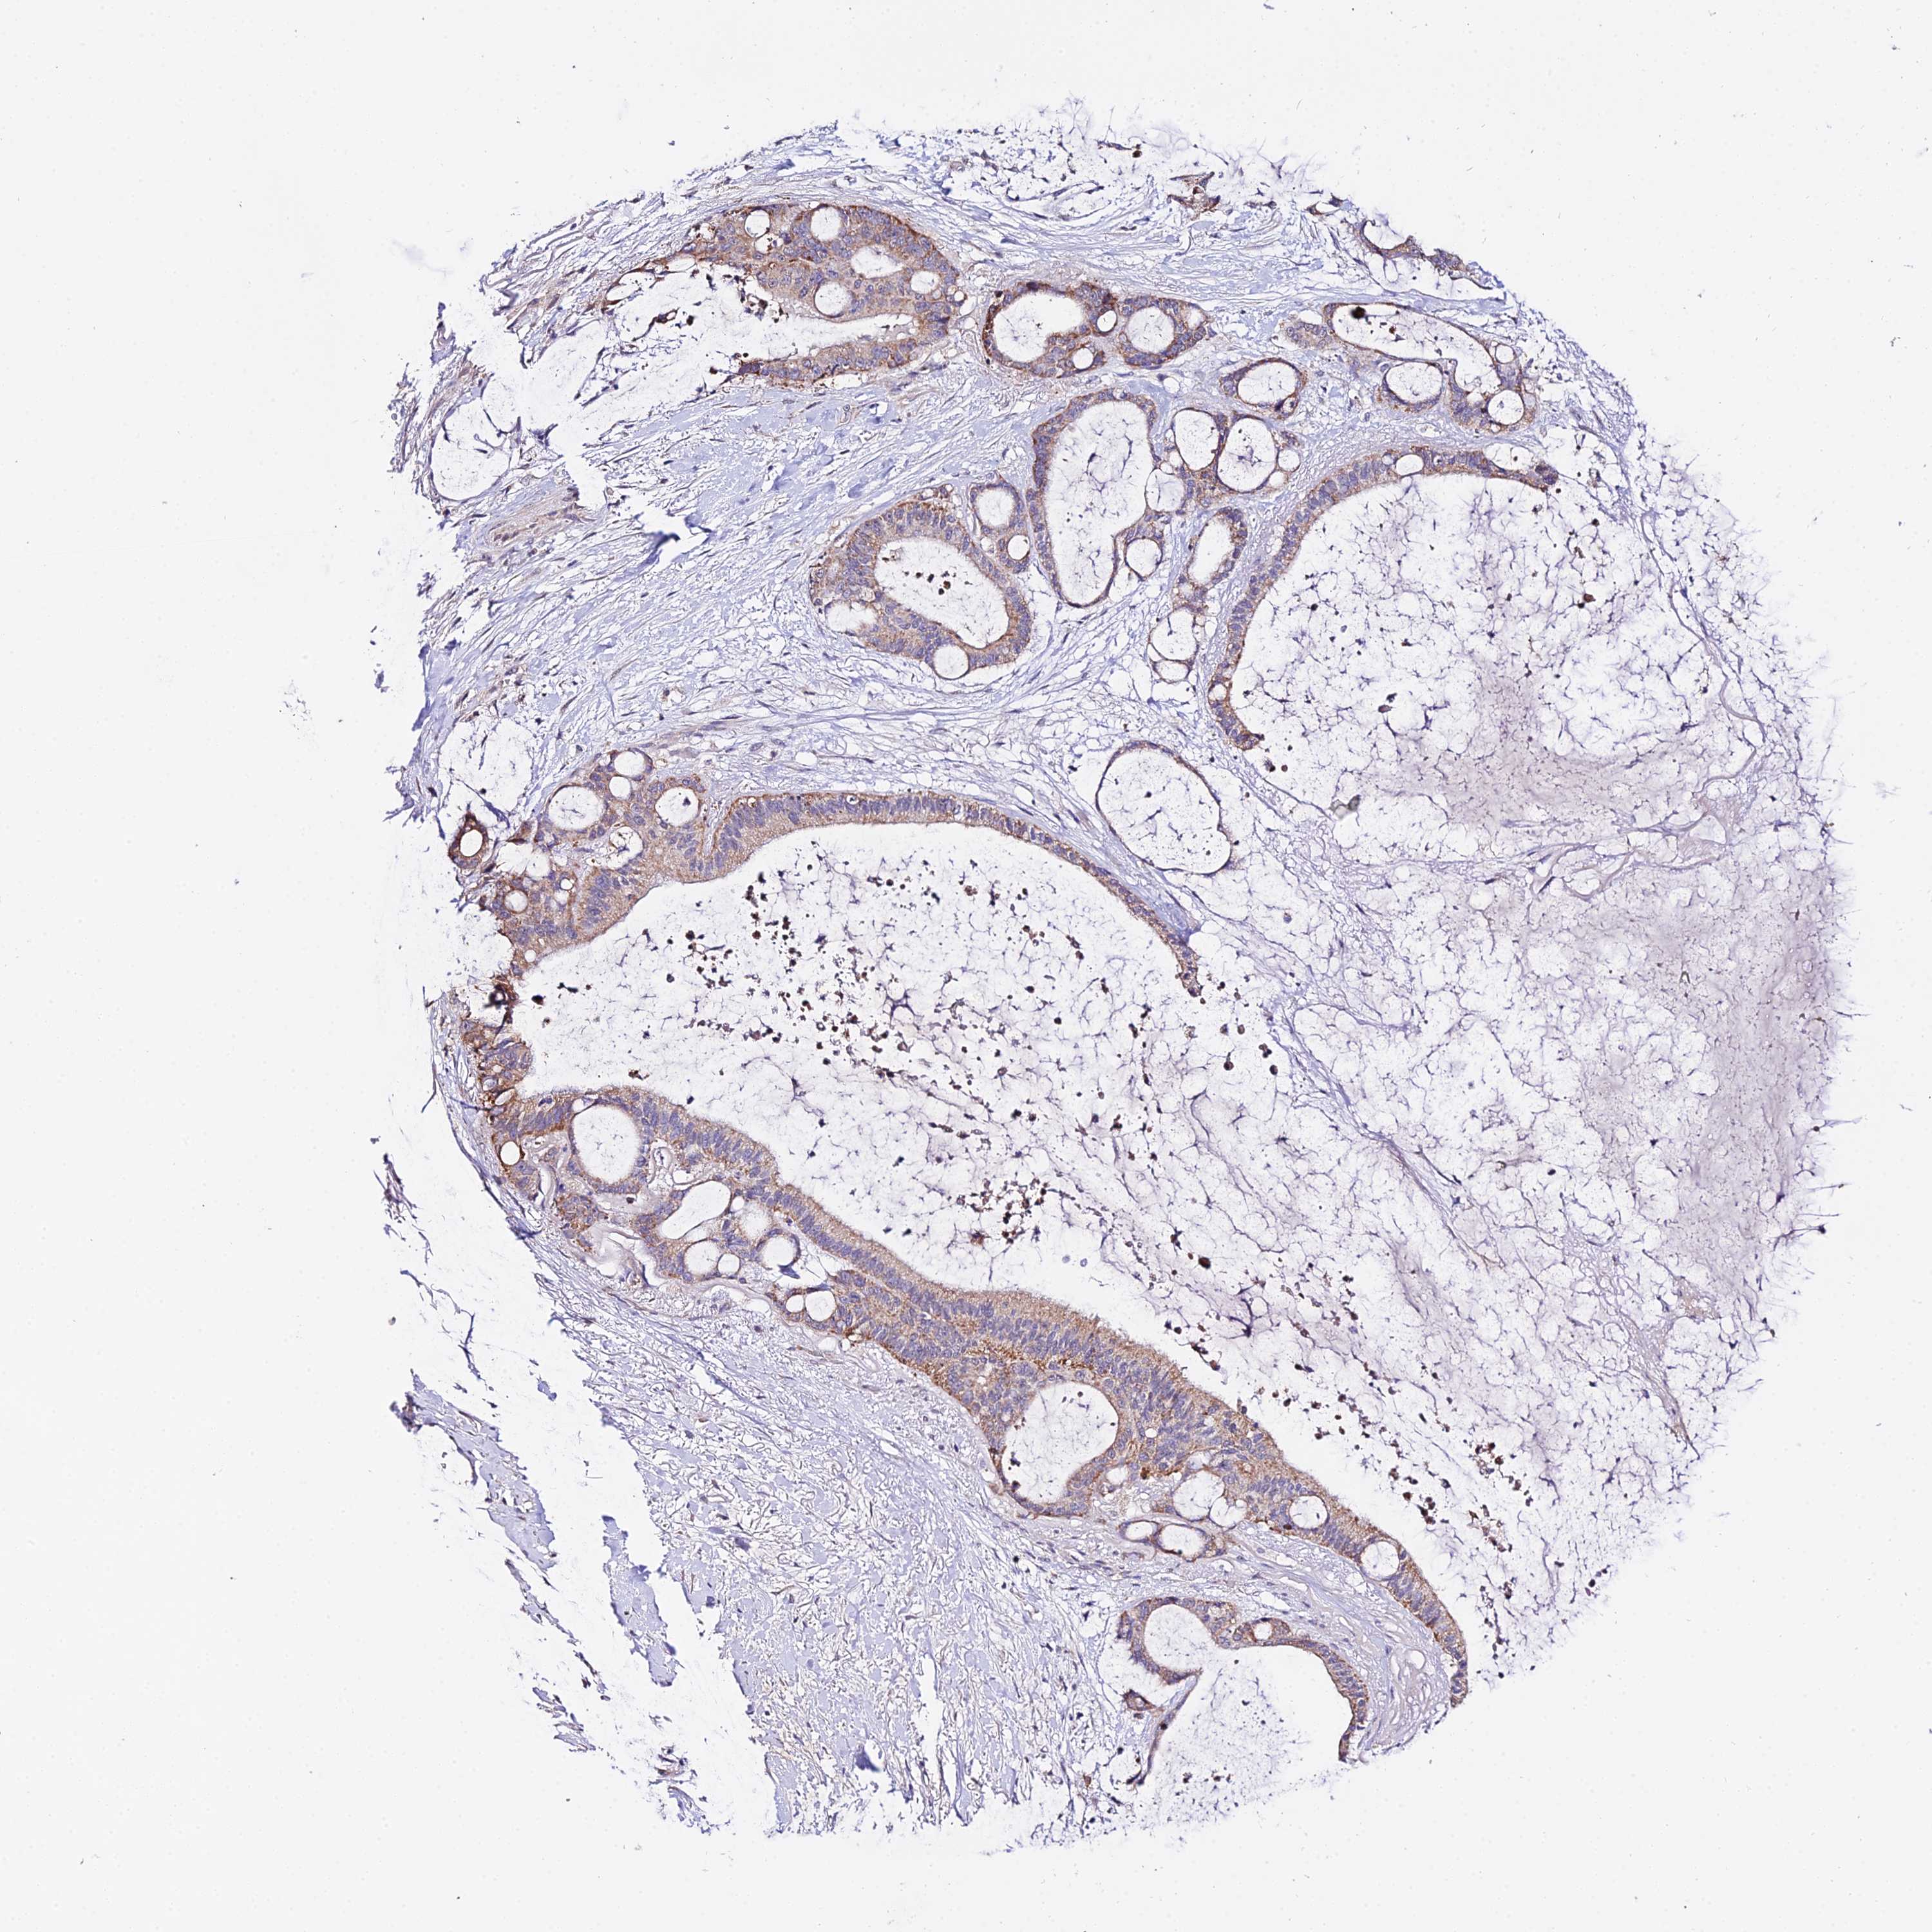

LIVER CANCER - Protein expressioni

A mouse-over function shows sample information and annotation data. Click on an image to view it in a full screen mode. Samples can be filtered based on level of antibody staining by selecting one or several of the following categories: high, medium, low and not detected. The assay and annotation is described here.

Note that samples used for immunohistochemistry by the Human Protein Atlas do not correspond to samples in the TCGA dataset.

Antibody stainingi

Antibody staining in the annotated cell types in the current human tissue is reported as not detected, low, medium, or high, based on conventional immunohistochemistry profiling in selected tissues. This score is based on the combination of the staining intensity and fraction of stained cells.

Each image is clickable and will lead to virtual microscopy that enables deeper exploration of all samples and also displays staining intensity scores, fraction scores and subcellular localization as well as patient and tissue information for each sample.

Antibody HPA042994

Staining

High

Medium

Low

Not detected

Intensity

Strong

Moderate

Weak

Negative

Quantity

>75%

75%-25%

<25%

None

Location

Nuclear

Cytoplasmic/membranous

Cytoplasmic/membranous,nuclear

Cholangiocarcinoma

Carcinoma, Hepatocellular, NOS